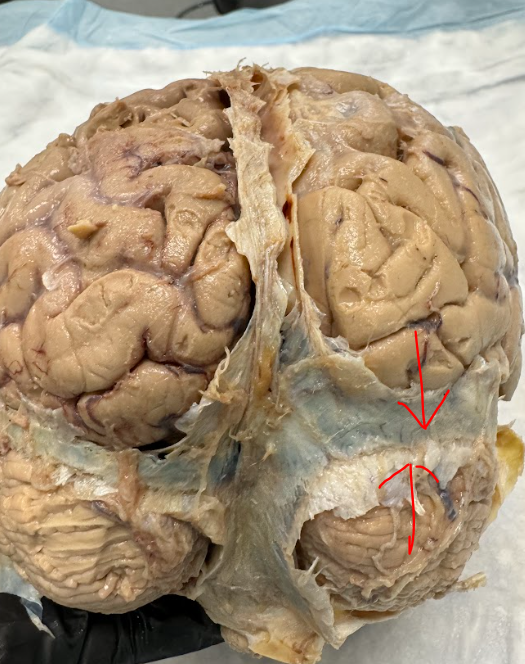

Edited: Facial N